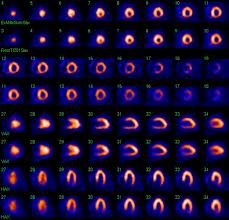

- Nuclear Cardiology Lab (Thallium Stress, Dobutamine Stress, Adenosine Stress, Dipryridamole Stress)

Nuclear Cardiology Testing Echocardiography Varicose Vein Ablation During a nuclear heart scan, a safe, radioactive material called a tracer is injected through a vein into your bloodstream. The tracer then travels to your heart. The tracer releases energy, which special cameras outside of your body detect. The cameras use the energy to create pictures of different parts of your heart.

This test is used to determine if you have obstructed coronary arteries that may cause you to be experiencing chest pains. This condition may lead you to sustain a heart attack. This especially useful for people experiencing chest pain. Echocardiography is a diagnostic test that uses ultrasound waves to create an image of the heart muscle. Ultrasound waves that rebound or echo off the heart can show the size, shape, and movement of the heart's valves and chambers as well as the flow of blood through the heart. Echocardiography may show such abnormalities as poorly functioning heart valves or damage to the heart tissue from a past heart attack.